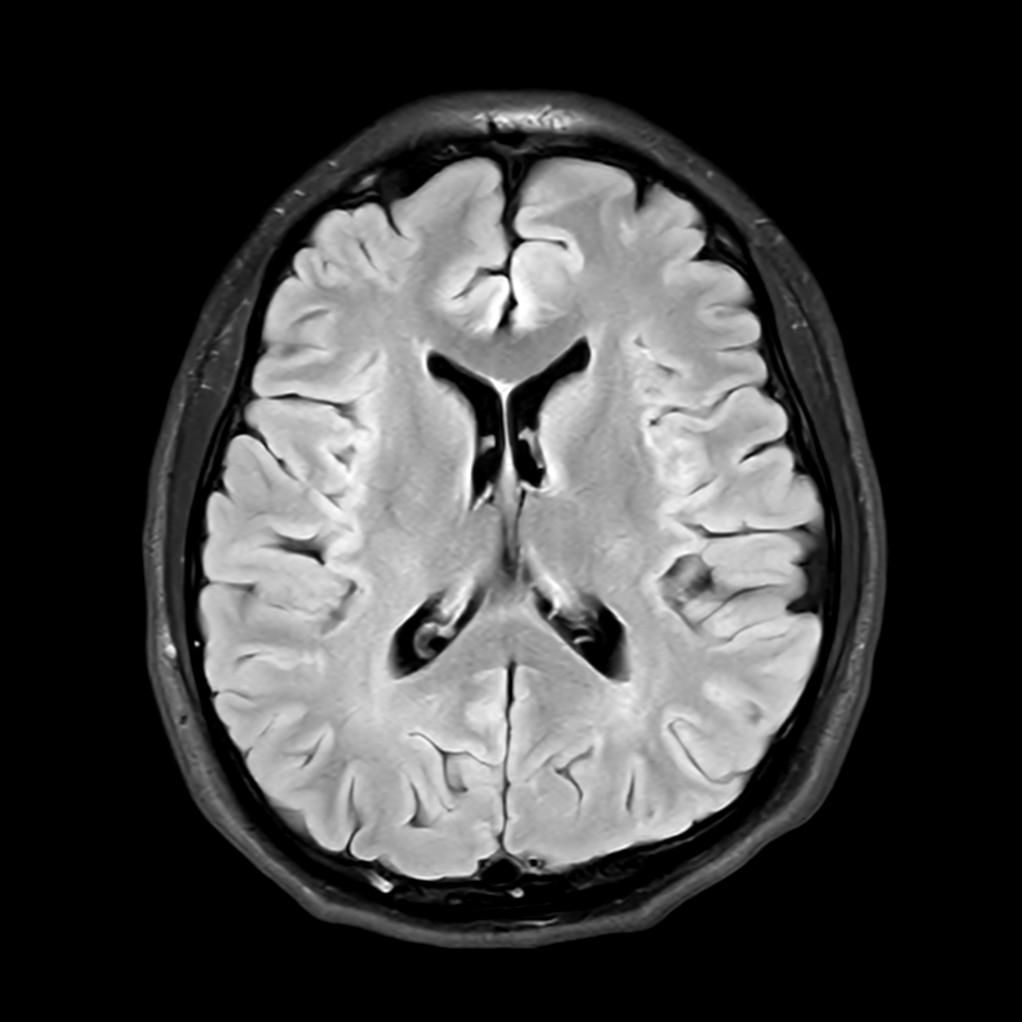

뇌 mri / 두정엽 부분 병변이나 위축되었는지요?

시공간 감각 저하(비현실감)와 바보가 되는 느낌(?)으로 최근에 mri를 촬영하였는데, 사진상 오른쪽에 구멍이 나있어서.. 질문드립니다.

• 1번 째 사진

저부분은 특별히 어디가 이상이 있거나 하는 것은 아닙니다.

그래서 환자분의 현재 증상에 대해서는 다른 접근을 해보셔야 하겠습니다.

정신과 진료도 한 번 고려를 해보시면 도움이 될 것 같습니다.